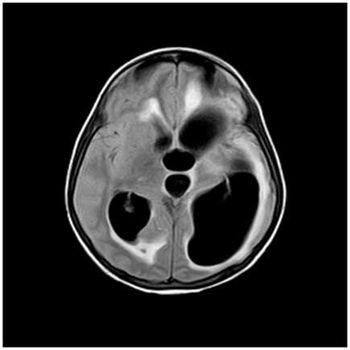

Case History: 42-year-old patient presents with complaints of headache.